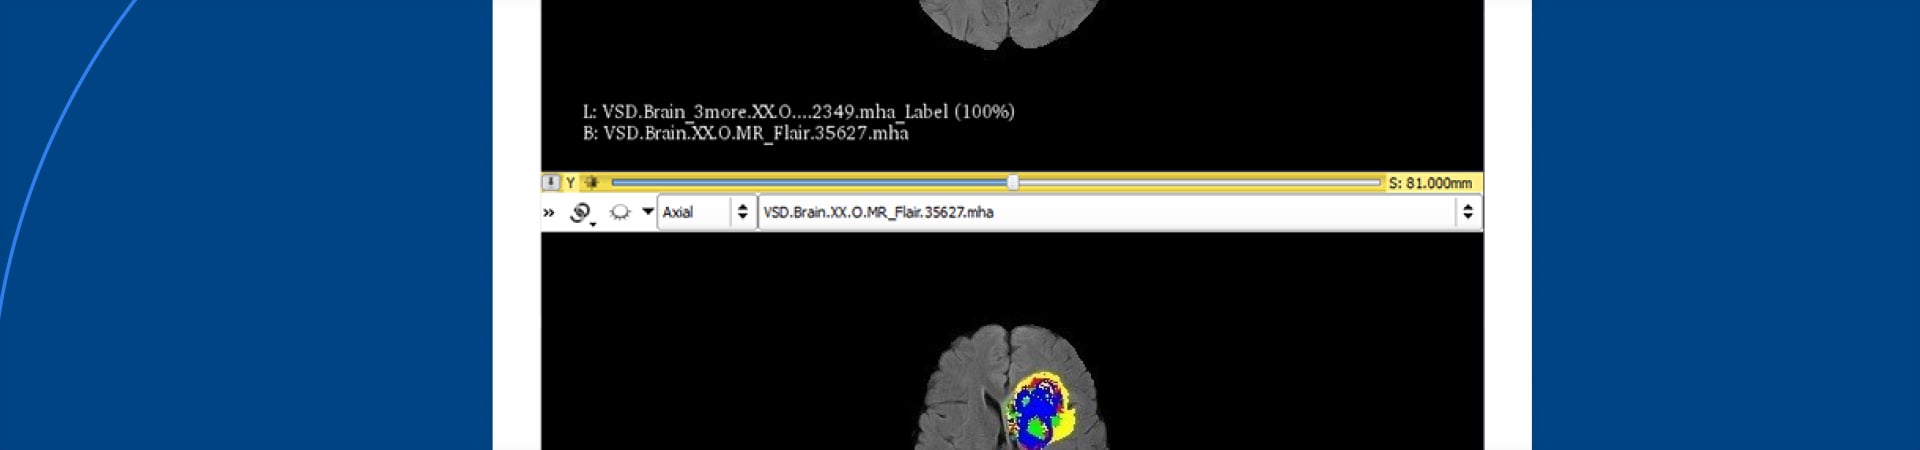

The automated medical diagnostics application was to analyze uploaded brain MRI scans and mark the scanned area with the segmented tumor, including each tissue type defined – normal tissue, edema, nonenhancing core, necrotic core and enhancing core.

To evaluate CNN performance, the team compared acquired results with the ground truth. The ground truth was taken from BRATS imaging datasets, which have been segmented and annotated manually by one to four raters as well as approved by neuro-radiologists. The maximum network accuracy achieved is 87%.

Comparison: ground truth (top) and the project result (bottom)